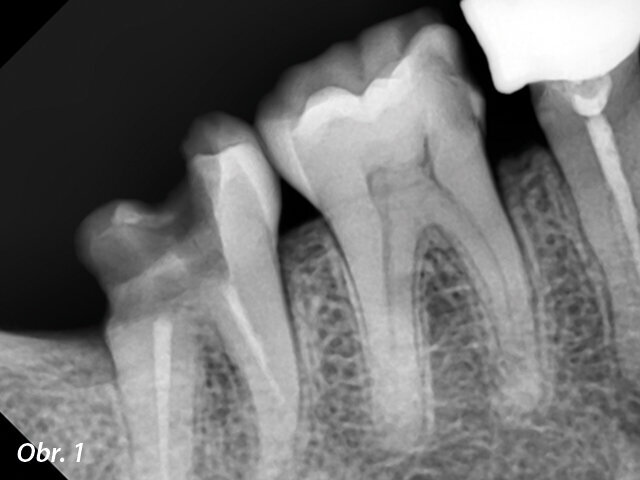

Na naši zubní kliniku se dostavila 42letá pacientka a uváděla problémy související s pravým prvním dolním molárem. Standardní chladový test zubu 46 prokázal opožděnou reakci. U preoperačního rentgenového snímku byla patrna neobvyklá anatomie zubu a stanovena diagnóza. Ačkoli se anatomické markanty liší případ od případu, typický molár obvykle nemá v systému kořenových kanálků více než čtyři hlavní kanálky. Avšak model meziálního kořenového kanálku u dotyčného moláru vykazoval některé významné postranní struktury. Rentgenový snímek se téměř podobal chobotnici s mnoha chapadly (obr. 1). Byla diagnostikována akutní pulpitida a pacientka následně souhlasila s nechirurgickou endodontickou léčbou kořenového kanálku.

Preoperační rentgenový snímek zubu 46. Obr. 2: Meziálně excentrický rentgenový snímek s pěti viditelnými kořenovými kanálky.